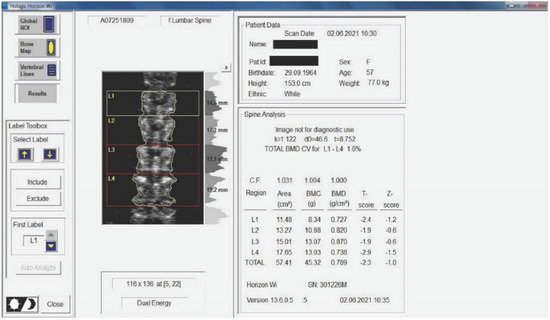

Twenty-nine non-smoking women with postmenopausal osteopenia/osteoporosis, a body mass index (BMI) of ≤25, and no physical exercise contraindications were included in the study. The subjects had not participated in any exercise program in the last 3 months, and all of them were sedentary people (less than 60 min of exercise per week). BMD was measured using DEXA analysis (Hologic Horizon, Santa Clara, CA, USA) and radiological examination (see Figure 1 and Figure 2). Skeletal BMD can be measured using DEXA, which is considered by some authors to be one of the most effective methods of diagnosing osteoporosis or osteopenia [8]. Currently, DEXA is the standard reference for diagnosing osteoporosis [9,10]. It is a precise evaluation method that involves exposing the areas to be evaluated to a small amount of X-rays and allows the areas of interest to be objectively measured. In this method, the two X-rays are absorbed differently in the bone, and the BMD is calculated in g/cm2 using simultaneous equations. Among the results offered by DEXA investigation is some information on bone mineral content (BMC) given in g, area measured in cm3, and BMD given in g/cm2 [11]. The measurement was compared with two reference values: one for young adults (30 years, which gives a T-score) and one for people of the same age as the evaluated person (which gives a Z score) [12]. DEXA has certain strengths, such as not exposing the patient to a high dose of radiation (1–6 μSv) and having a short time scan (1–2 min). Following the DEXA investigation, the software recorded the values obtained and displayed them on the screen. The T-score obtained by the subject being examined refers to her bone mass, taking as reference an individual of the same gender with peak bone mass. A classification was established depending on the score obtained: normal bone mass density (score between −1 and 0 or higher), osteopenia (between −1.1 and −2.4), and osteoporosis (a score of −2.5 or less). The Z score obtained refers to the BMD of the scanned subject compared with a subject of the same age and weight (see Figure 2).

Medical investigations (DEXA and radiographs) were conducted by a technician and the radiographs was interpreted by a specialist. The T-score provided information on whether the subject could be included in the study (the condition being that the subjects had osteopenia or osteoporosis), and the lumbar spine BMD was the quantitative information we used to make pre- and post-test comparisons. Table 1 and Table 2 and Figure 2 present information on BMD in each vertebra, but the last and the most important result is the total BMD, which is the reference result. With the help of radiography, we used visual information about the body and height of the vertebrae, the presence or absence of vertebral fractures, and the height of the intervertebral spaces. We could also observe if the subject had a history of other pathologies that would be a contraindication to performing the training protocol. Different from the DEXA investigation, which was made at the beginning and at the end of the study, the X-ray was used only at the beginning of the study to rule out the possibility of other pathologies in the lumbar area that could prevent the subjects from participating in the program.

Figure 2. Measurement of BMD for the subjects included in the study. The results are displayed planimetrically, relating the BMC to the surface being evaluated (g/cm2). This also gives us a total T-score expressing whether the person has normal BMD (T-score between −1 and 0 or above), osteopenia (T-score between −1.1 and −2.4), or osteoporosis (T-score of −2.5 or less). The results in the image show us that the subject has osteopenia (but is extremely close to osteoporosis).